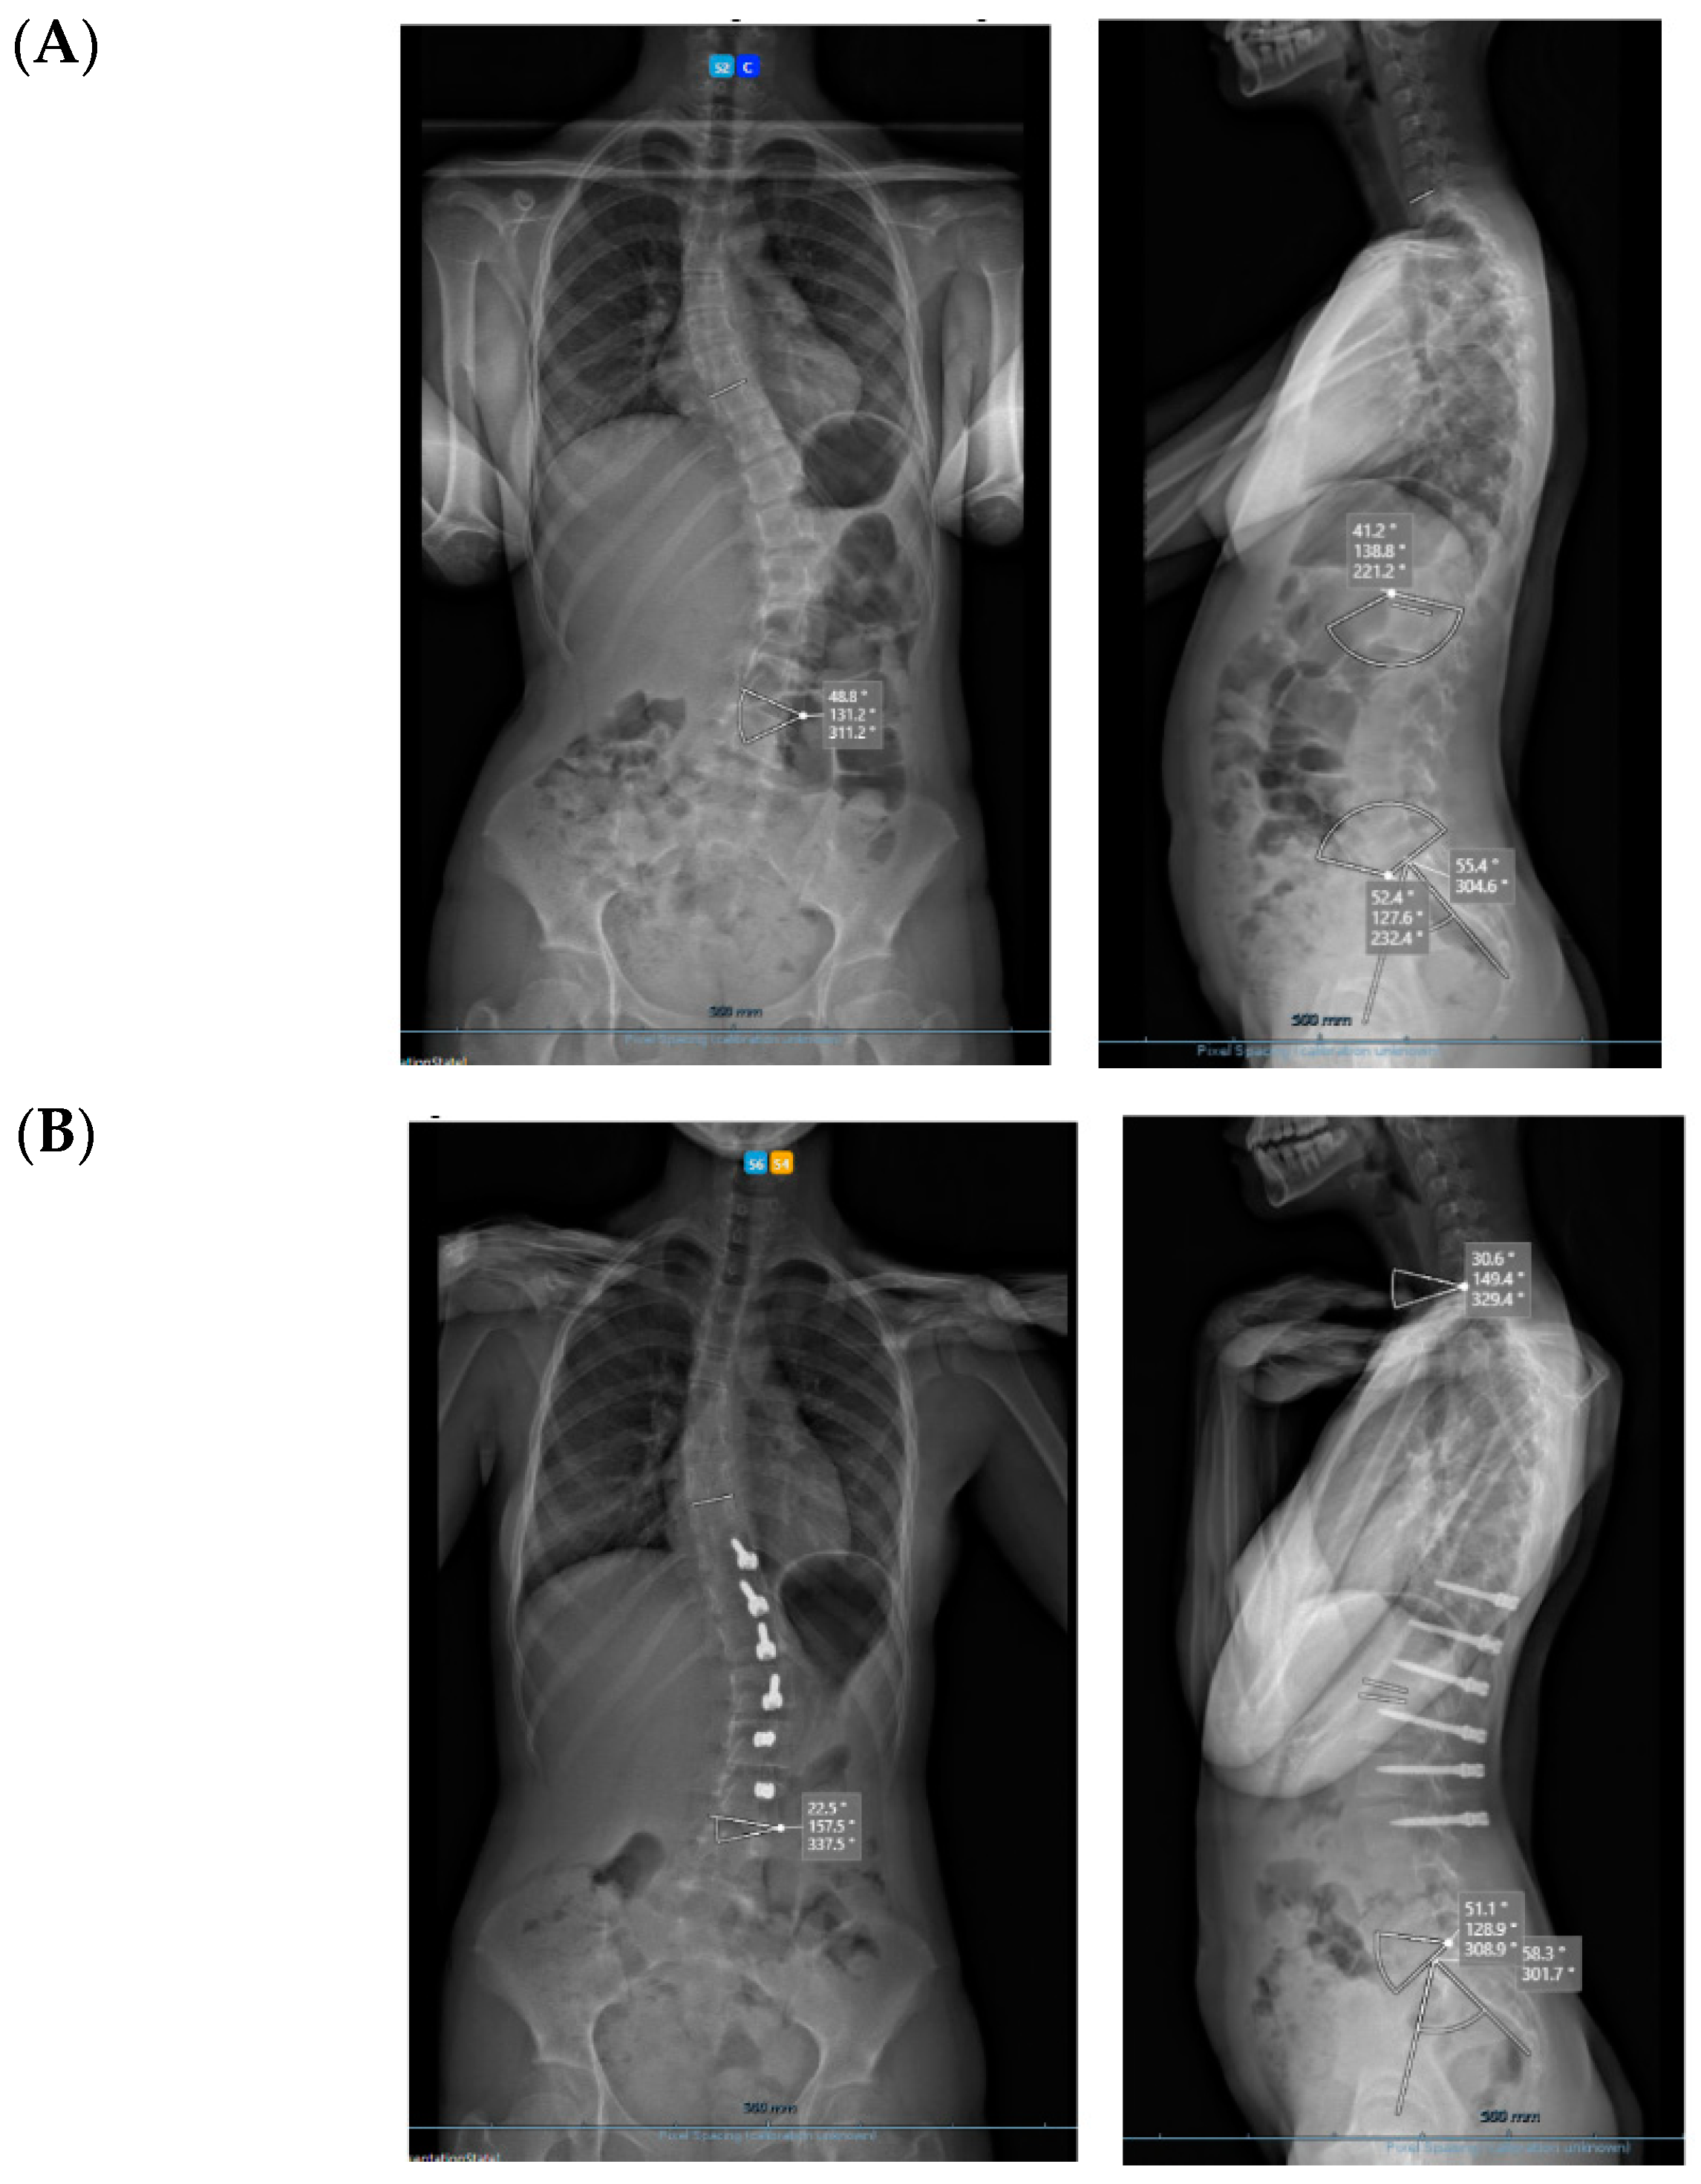

All three cases were thoracolumbar scoliosis (Lenke 5C) with an apex between T12 and L1 (Figure 3, Figure 4 and Figure 5).

Figure 3.

A 14-year-old adolescent. (A) Pre-op. (B) Immediate post-op. (C) One-year follow up.

Figure 4.

A 13-year-old adolescent. (A) Pre-op. (B) At 6-month follow up.

Figure 5.

A 14-year-old adolescent. (A) Pre-op. (B) At 6-month follow up.

As far as skeletal maturity is concerned, two cases were Sanders 3 (Risser 1 and 0) and one case was Sanders 5 (Risser 4).

3. Results

All cases have progressed well with improvement of the curvatures with growth (Table 1) both in the coronal and sagittal alignment. At the 6-month FU, there was a mean 67.5% (34.8°) improvement in the main Cobb angle, but at 1 y, the oldest case over-corrected, and this was clinically noted by the girl, who pointed out that her flank symmetry had recently inverted (from one side to the other) after being symmetrical for some time (Figure 6).